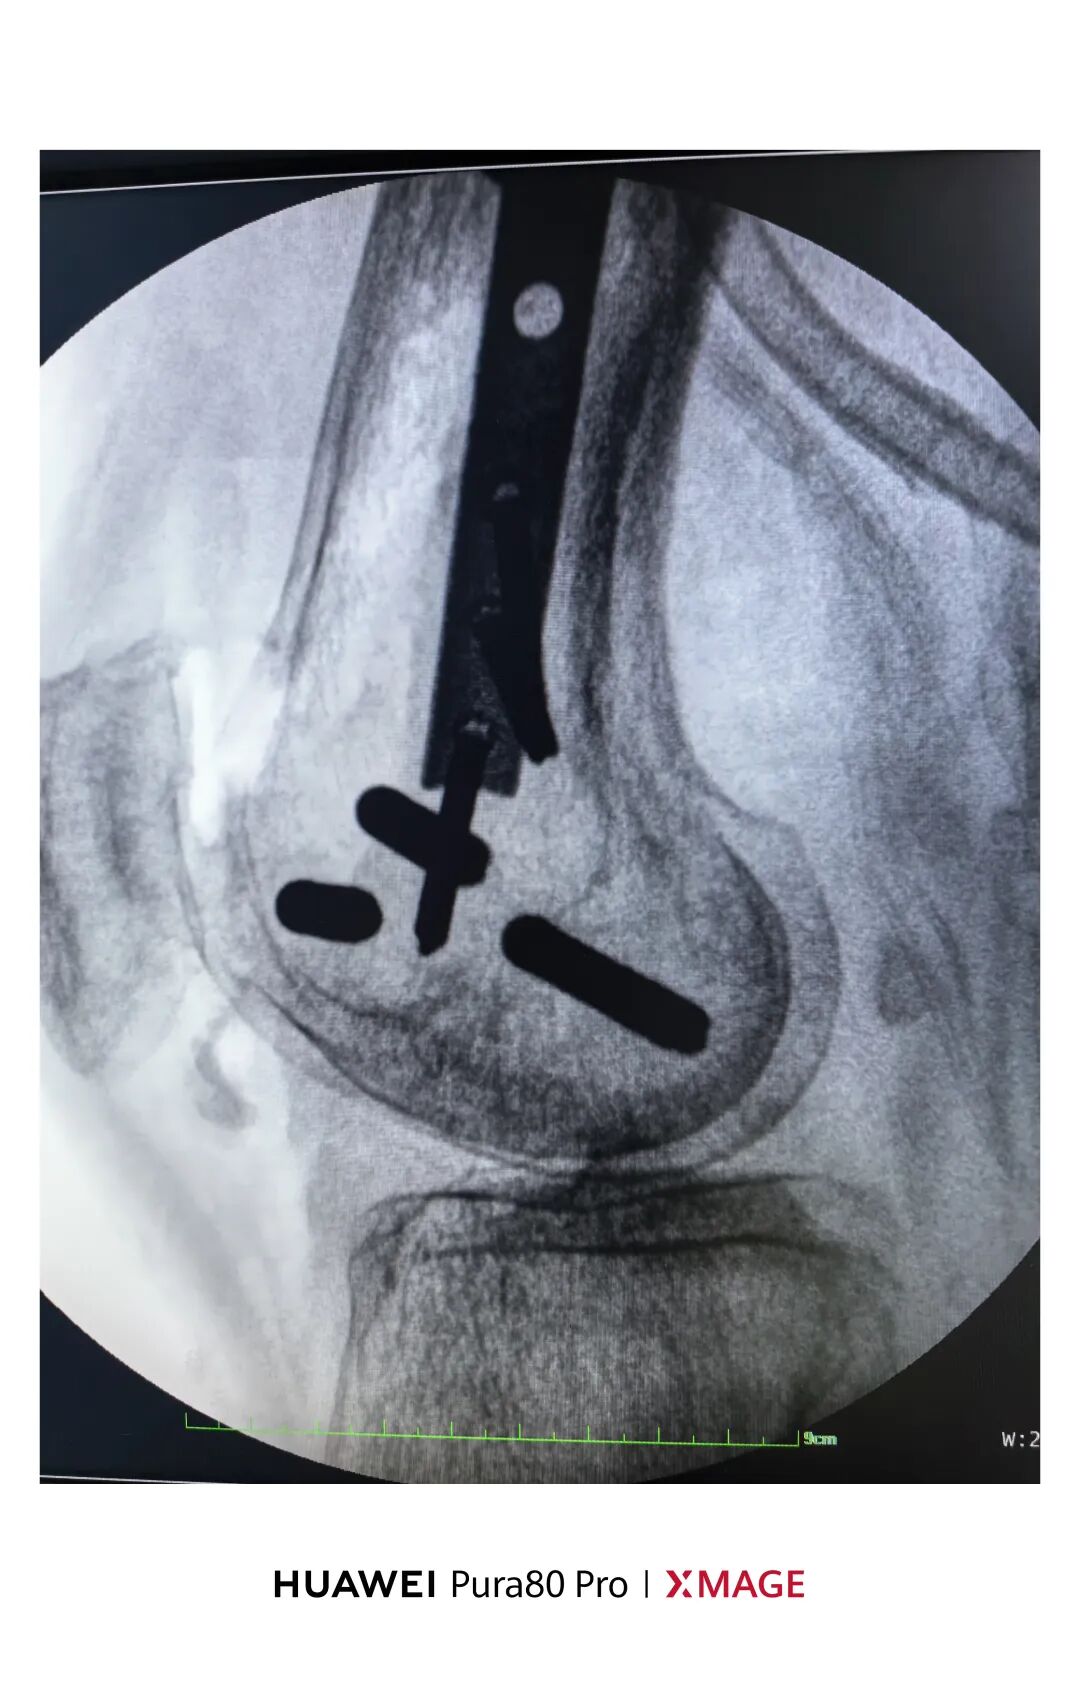

5个月前在魔都骨折,当时建议手术

患者拒绝并签字

给予支具固定

现畸形、疼痛伴活动受限来院

复位满意,力线纠正